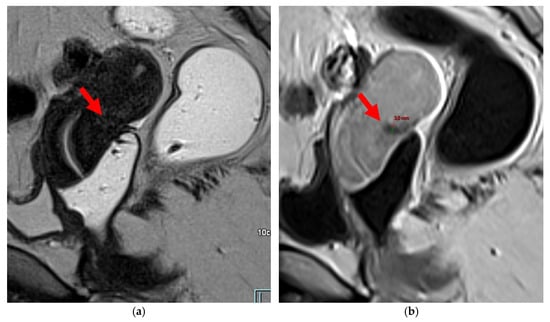

Figure 4. Pelvic MRI scans of seven patients with HTD type 3B USLs. (a) Sagittal T2WI: a thickened (2.1 mm) and stiffened right USL (arrowhead) with “bowstringing”. (b) Axial T2WI: a caliber disparity (dashed arrows) with focal thickening (4.2 mm) of the left proximal USL (arrowhead). (c) Sagittal T2WI: a caliber disparity (dashed arrows) with focal thickening (2.5 mm) of the right distal USL. (d) Axial T2WI: a right USL with a notched and irregular surface (dashed arrows). (e) Axial T2WI: thickened and stiffened left (3 mm) and right (2.5 mm) USLs with “bowstringing” of both USLs (arrowheads). (f) Sagittal T2WI: a thickened (2.6 mm) right USL with a stiffened appearance characterized by a steep vertical orientation (arrowhead). (g) Sagittal T2WI: the right USL appears thin (1.9 mm) but stiffened (arrowhead), exhibiting “bowstringing”. These findings led to its reclassification from type 2 to type 3B.